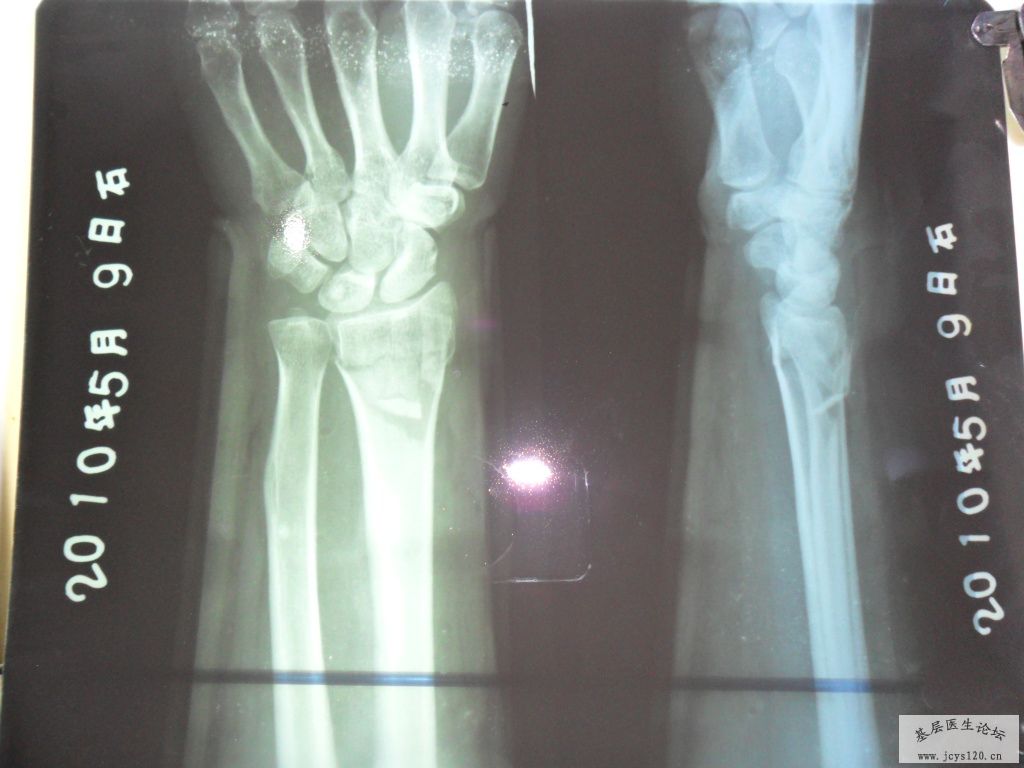

桡骨远端粉碎性骨折复位前后对比!一小时前急诊的病例!

一小时前,有一妇女因为去田间放水,不慎摔倒在田埂上,摔倒时因害怕伤着头,条件反射式的将右手撑在地上,右手剧烈疼痛,所以来诊,给予急诊X光摄片,呈右手远端粉碎性骨折,断端重叠移位,并有小块碎骨片嵌插在断端,片照好后,由我和助手握住右手骨折端两侧开始徐徐用力做拔伸牵引,我估计到重叠的断端分离后,将患者的手呈后前位,(掌心向上),再在骨折端施行了正骨八法中的某些手法,复位好后,敷上中药,夹板,再复查了一张X光片子,15分钟后,片子出来一看,复位一次成功,达到功能复位,随后开了3天的西药让病人回家去了,以下是该患者的片子: